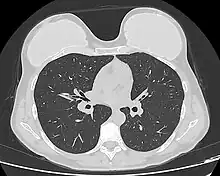

Computed tomography of a woman with breast implants

Implant rupture visualized by breast computed tomography